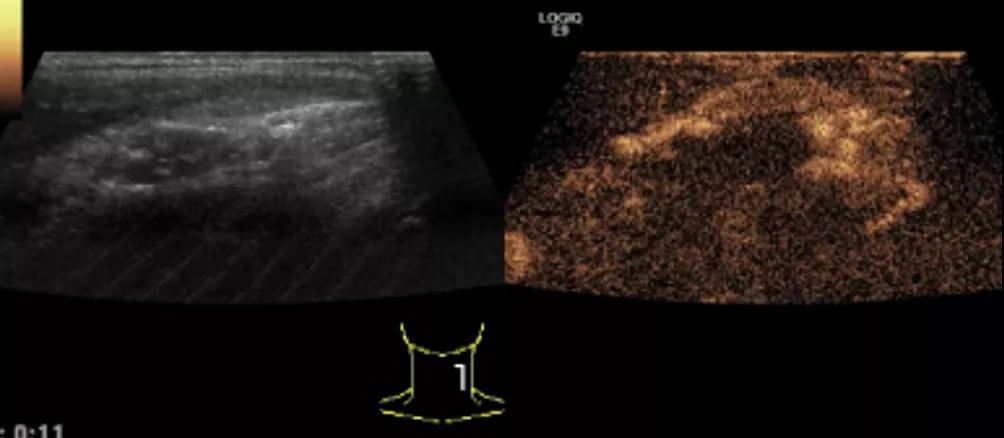

随后,徐栋教授进一步分享了五个临床实战病例,带来了更直观的热消融治疗经验。第一个病例是62岁肺癌患者,术后1年余发现双侧锁骨上淋巴结复发,侵犯神经,存在静脉回流、淋巴回流障碍,肿胀、疼痛非常明显。影像显示患者淋巴结边界不清、形态不规则,存在浸润,血流强化增强。由于患者在系统治疗后进展,且主要目的缓解症状、减瘤。局麻下行热消融术,从后向前逐层消融,热消融之后超声造影即刻评估显示完全充盈缺损,完全覆盖病灶。

(病例1图例)